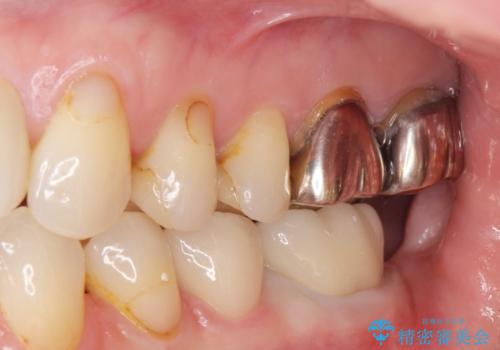

- 銀歯のやりかえ希望の患者様です。

症状もなく、レントゲンでも根尖病巣が見られないため

患者様と話し合った結果、中の土台は外さず、被せ物のみのやりかえとなりました。